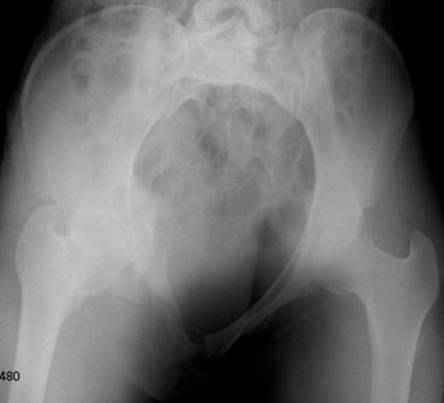

Серия до- и послеоперационных снимков этой пациентки. Хотя бы post factum обсудить. Не знаю, что можно сделать с задними отделами стержневым аппаратом, но три крепких парня открытым путем с помощью "волшебных" слов еле-еле смогли отрепонировать - сзади все было очень ригидно!

Здравствуйте, Евгений! У меня видна только дооперационная проекция inlet.